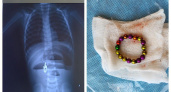

В Чувашии более 20 детей пострадали, глотая магнитные шарики, проволоку или бусины

15 августа 2024